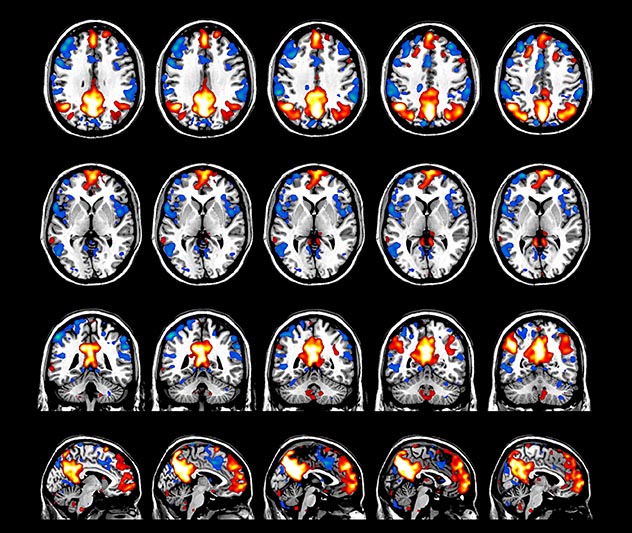

The fMRI pulse sequence was a single shot FFE echo planar acquisition using MultiBand SENSE factor 5, dS SENSE factor 1.25, isotropic voxel size 2.7 mm, 50 transverse slices, TR 700 ms, TE 30 ms, flip angle 52 degrees, 765 dynamic scans, total scan duration 9:01 minutes. Image provided by Matthan Caan, PhD, Assistant Professor at the AMC.

Imaging was performed using Ingenia 3T CX with a 32ch dS Head coil, TR 1.6 sec, TE 35 ms, voxel size 3.1 x 3.1 x 3.1 mm, 46 slices and Multiband SENSE factor 2. Image provided by Dr. Gispert

Default mode network as discovered by resting state fMRI in one participant of the ALFA cohort [7]. rs-fMRI allows us to find networks of brain regions with highly correlated activity and sustaining distinct brain functions. The default mode network (in warm color scale) is active when the brain is focused on introspective thinking and has been shown to be altered in Alzheimer’s. Interestingly, brain areas of this network are known to show abnormal levels of one of the pathological hallmarks of Alzheimer’s (b-amyloid deposition) in preclinical stages. We want to better understand the alterations of these brain networks in preclinical stages of Alzheimer's and explore their potential use as biomarkers.